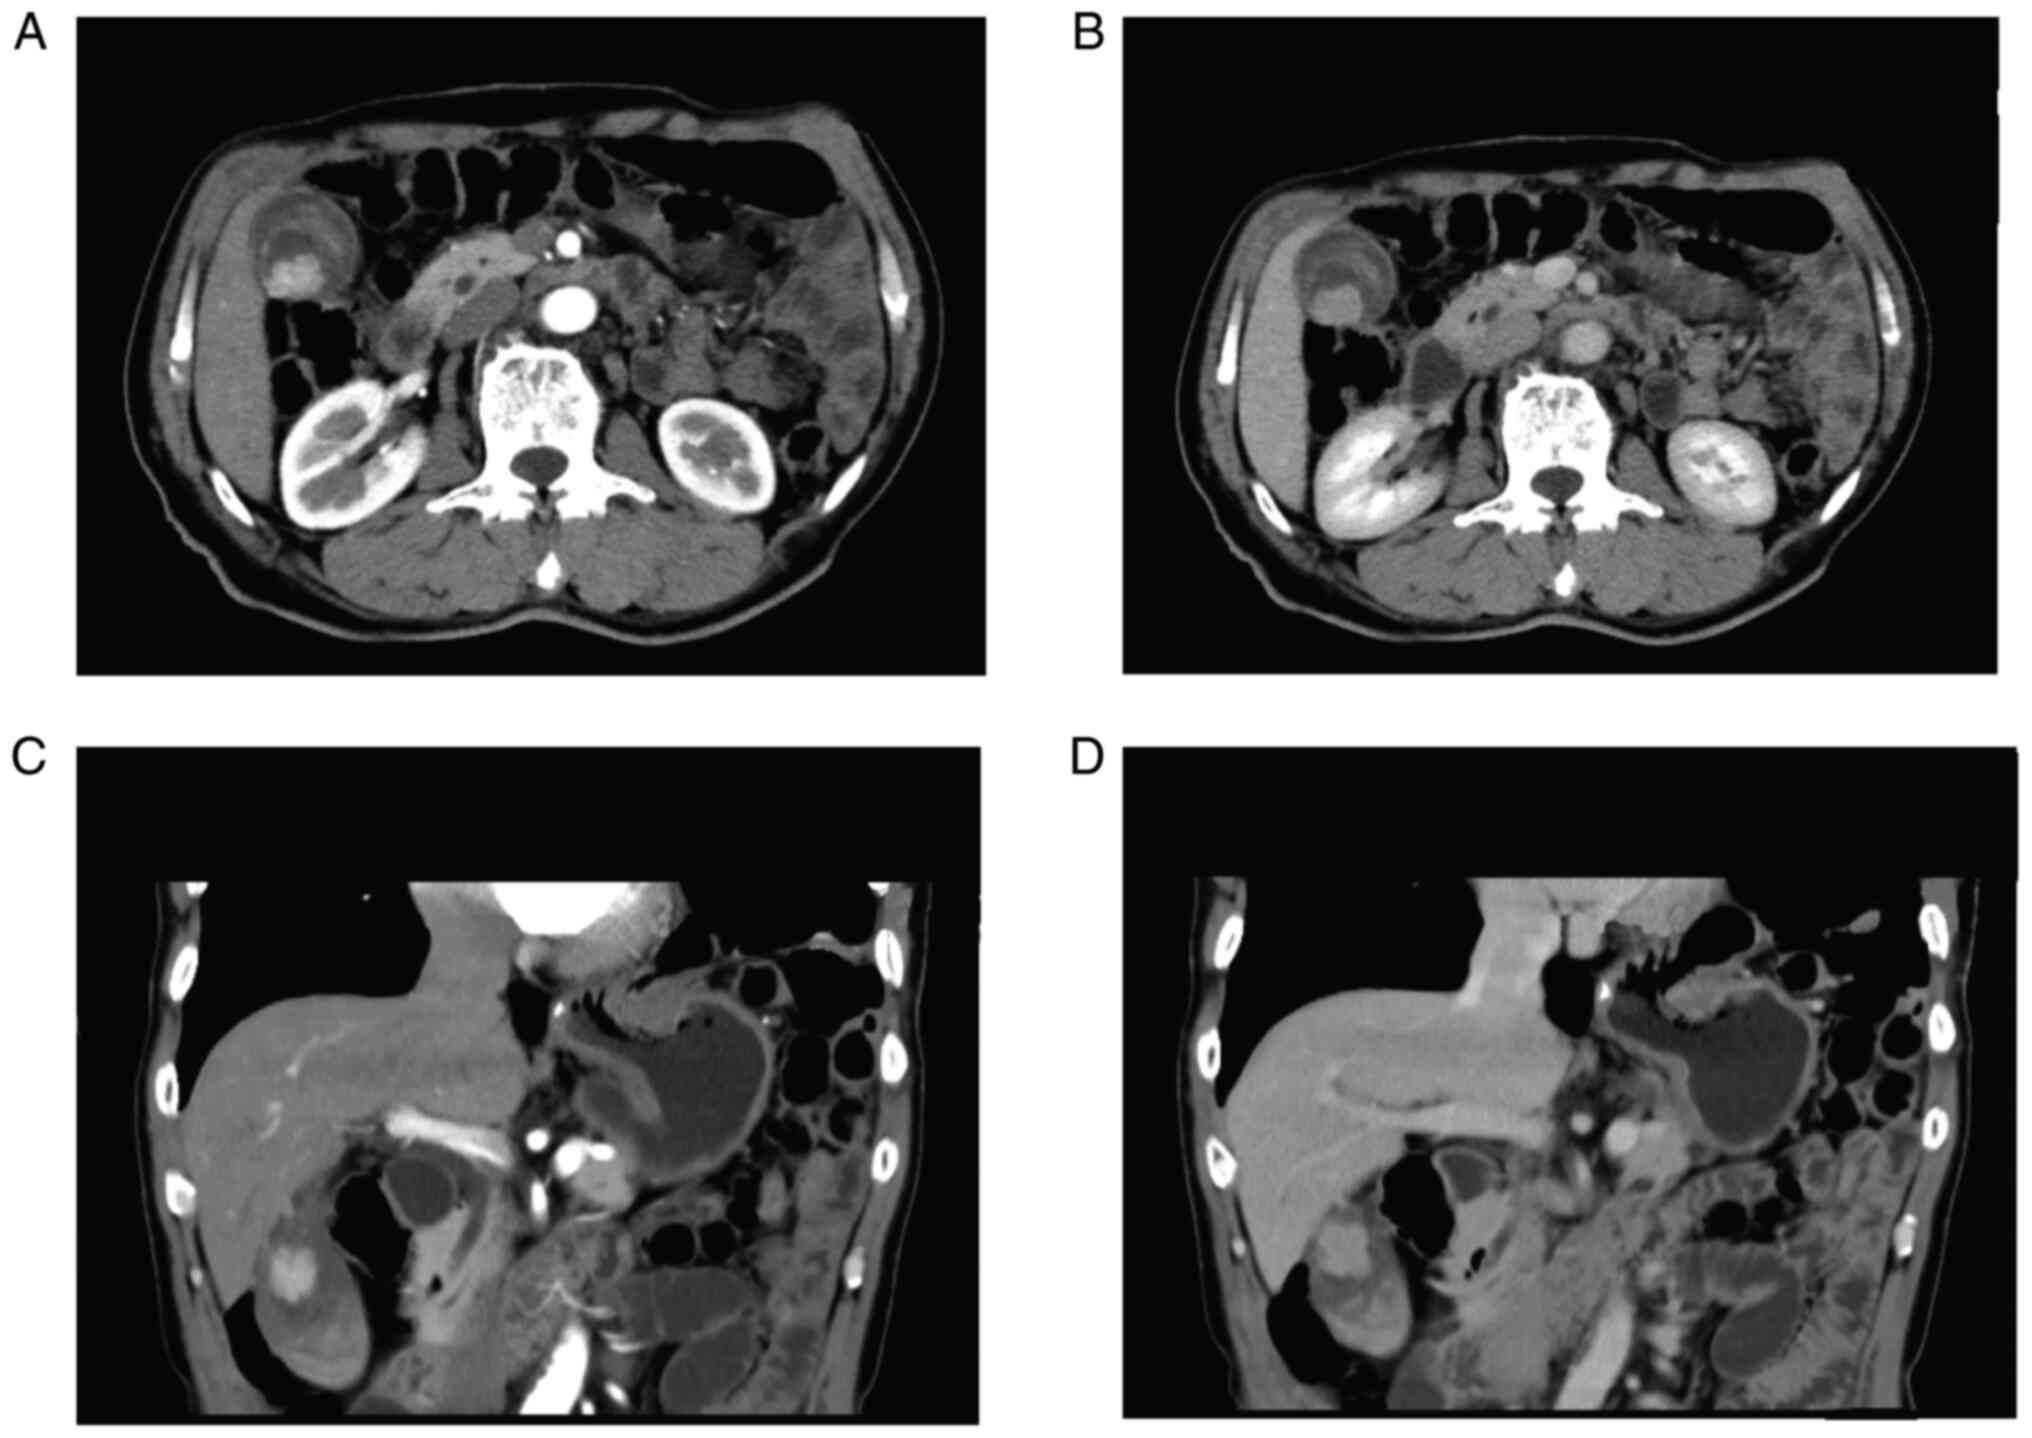

The case was a 65-year-old male patient with no family history of cancer and with a past medical history of appendectomy and surgery for lumbar disc herniation. Suspected gallbladder malignancy was found during physical examination. He had no fever, abdominal pain, nausea, vomiting, weight loss and other complaints. No abnormal clinical signs were detected by abdominal examination. Computed tomography (CT) scanning of upper abdomen indicated soft tissue shadows could be seen at the bottom of the gallbladder, invading the liver, and the boundary was blurred. In addition, a cyst was found in the left lobe of liver. Contrast-enhanced CT scanning indicated significant uneven enhancement and it was about 60×45 mm in size (Fig. 1). Preoperative positron emission tomography/computed tomography (PET/CT) showed irregular soft tissue occupancy at the bottom of the gallbladder with abnormally high metabolic activity and low-density occupancy in the lower right anterior lobe with abnormally inhomogeneity high metabolic activity (Fig. 2). Levels of tumor markers were shown in Table I. All these results suggested that gallbladder malignant lesions with the right liver lobe involvement. CT provided no clear evidence of distal metastases.

Figure 1.

CT images of case 1. (A) Cross-sectional contrast-enhanced arterial phase CT of the abdomen. (B) Cross-sectional contrast-enhanced venous phase CT of the abdomen. (C) Contrast enhanced arterial phase CT scan of the abdomen, coronal view. (D) Contrast enhanced arterial phase CT scan of the abdomen, coronal view. CT, computed tomography.